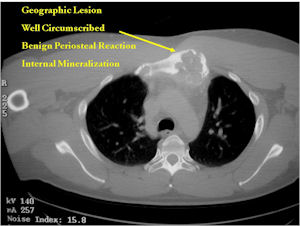

Plain X-rays:

- Geographic, circumscribed lesion usually around 5cm in size.

- There may be expansion of bone, cortical thinning and cortical breakthrough. A soft tissue mass may accompany this lesion but the soft tissue component is usually contained by the periosteum.

- The periosteum remains intact around the soft tissue component. Might need a CT scan to detect the subtle calcification (Egg Shell Rim of Calcification) associated with an intact periosteal reaction

- The lesion may be entirely radiolucent but usually shows some degree of mineralization. Mineralization may appear stippled like cartilage but do not see chondroid pathologically. Mineralization is sometimes better detected on a CT scan rather than an x-ray.

- Usually less surrounding sclerosis than an osteoid osteoma.

CT Scan:

- More useful for detecting mineralization and evaluating extent of bone destruction than plain X-ray